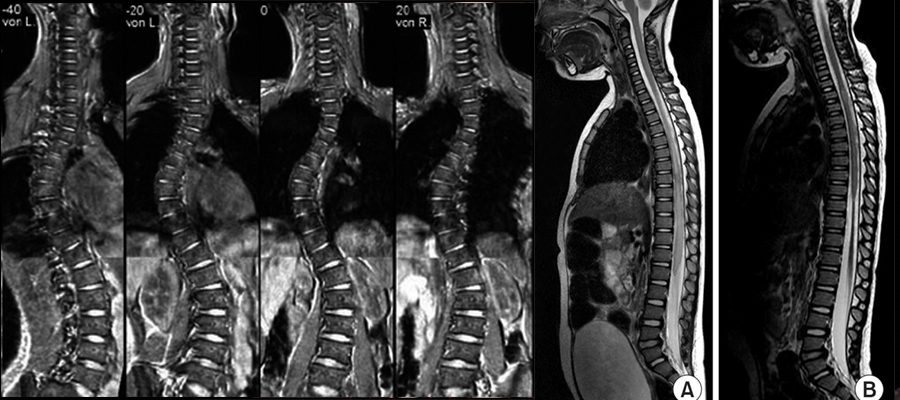

TÜM SPİNAL ( Tüm Omurga ) MR

Tüm omurga MR’ı yaklaşık 1 saat sürmektedir.Tüm omurilik kanalı ve omurgalar dahil ,omurların çevesindeki yumuşak dokuyu göstermektdir.

Skolyoz, kifoz gibi  tüm omurgayı aynı anda görebilmeyi gerektiren olgularda yapılır.Yeni teknoloji sayesinde  boyun,sırt ve bel için ayrı ayrı alınmış görüntüler birleştirilerek tüm omurga aynı anda görülebilir.

Ayrıca kanser hastalarına da kemik sıçraması yönünden tarama amaçlı yapılabilir.